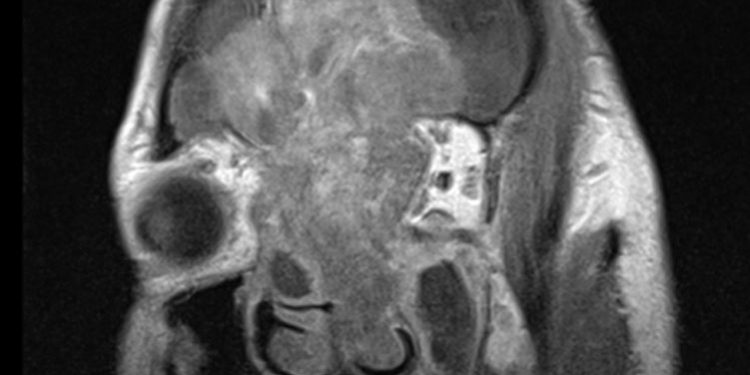

Μετεγχειρητικά σαφής βελτίωση της όρασης και των λοιπών συμπτωμάτων.

Εικόνα 3: Μετεγχειρητική απεικόνιση η οποία αναδεικνύει την αφαίρεση του όγκου (Προσωπικό αρχείο νευροχειρουργού Π. Σταυρινού).